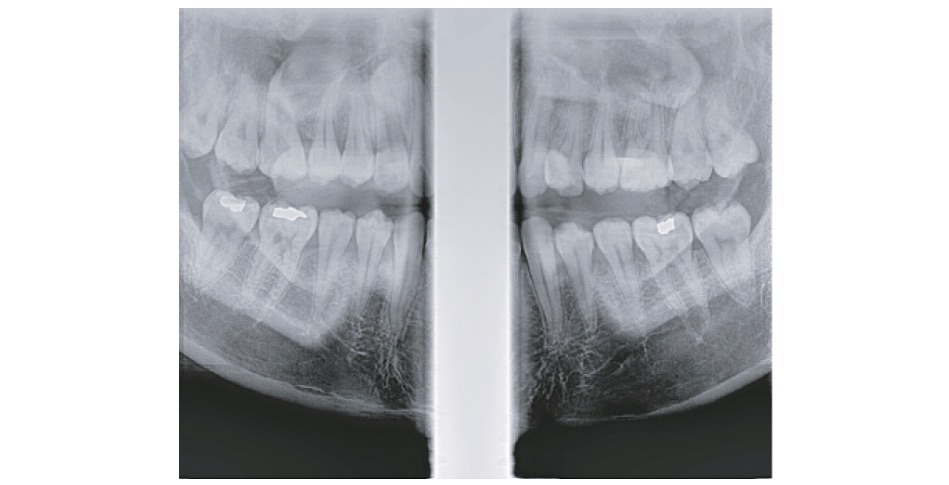

分割パノラマ撮影